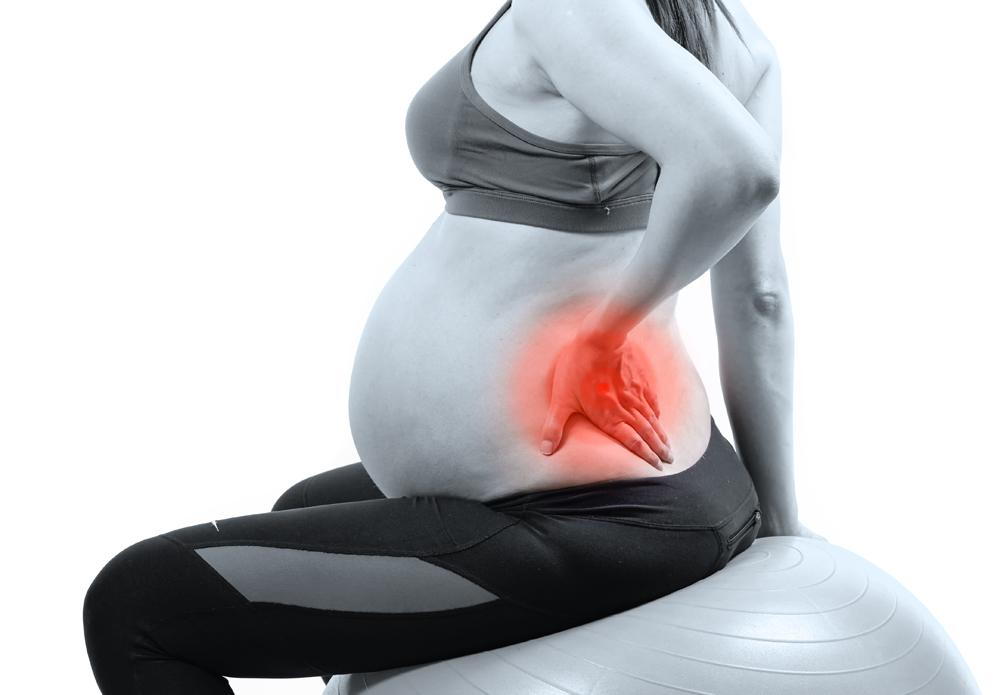

کمردرد در حاملگی

کمردرد در حاملگی: علل و روشهای پیشگیری و درمان کمردرد یکی از مشکلات رایج در دوران حاملگی است که بسیاری از مادران باردار آن را تجربه میکنند. این درد میتواند به دلایل مختلفی ایجاد شود و به طور معمول در سهماهه دوم و سوم حاملگی بیشتر به چشم میخورد. در این مقاله، به دلایل بروز […]